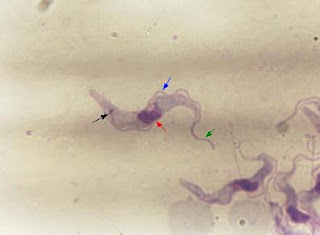

Trypanosoma cruzi:

Azul: membrana ondulante

Verde: flagelo

Rojo: núcleo

Negro: cinetoplasto